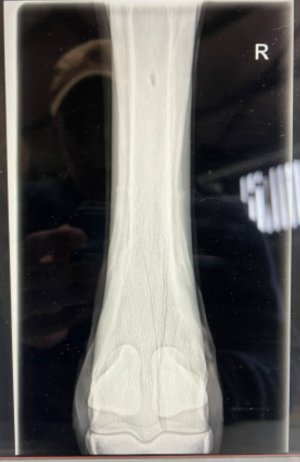

Omg I just realised whatever I just marked goes all the way up the leg 🙈

It does. So this horse started off with a splint bone fracture. At their 4 week xray check up we saw the horizontal crack all the way across the bone too. If that had moved or displaced the horse would be dead. Luckily for the horse we spotted it when we did, wrapped it back up for a few weeks, rehabbed and they raced on for another couple of years. It's a really weird rare one as they rarely crack horizontally without it being fatal. It wasn't seen at he first xray as you don't always see the full extent of the damage for a few days. So it will have been sitting their waiting to show.